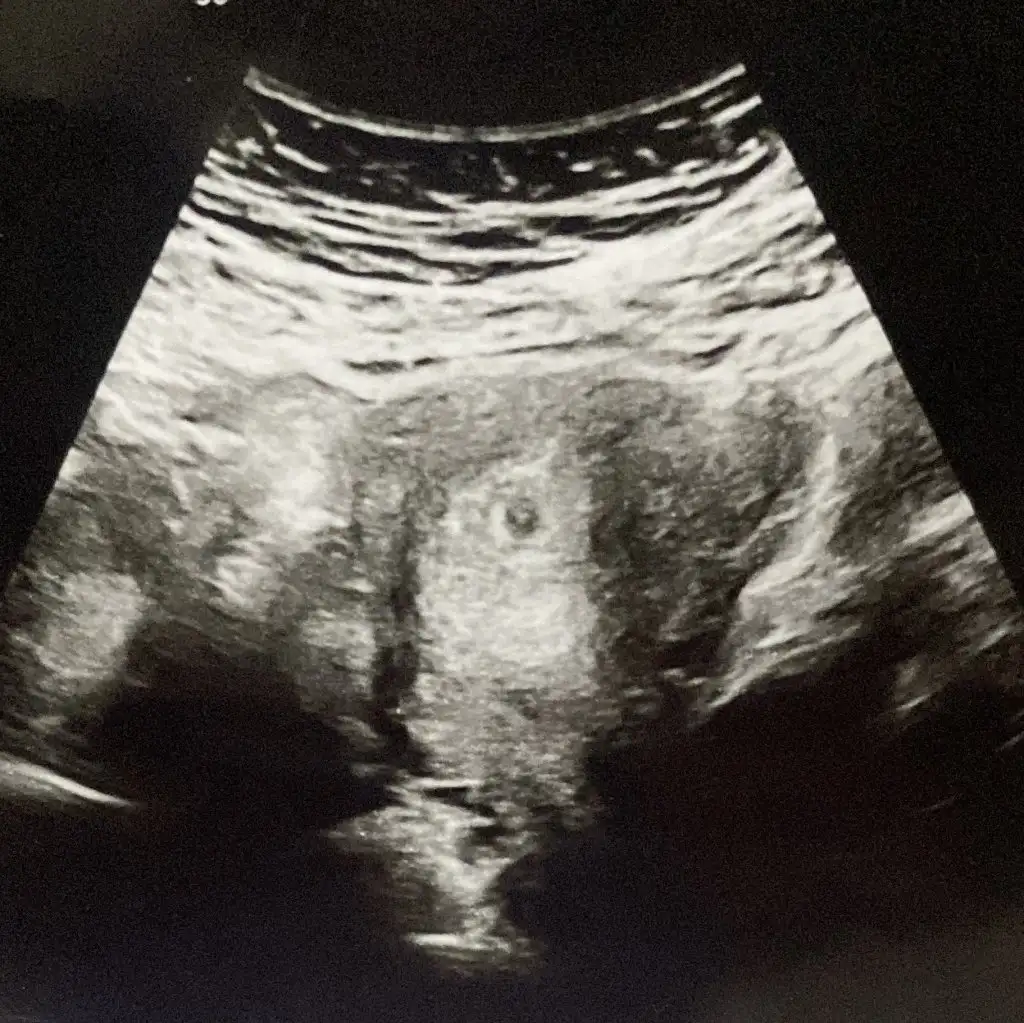

Aha da şu yani belli sende de 😅

Kızlar benim kesenin içinde birsey görüyor musunuz peki 🥹🧡

Eklentiler

• 680221E5-A673-45DA-98A9-1629644C9D13.webp

680221E5-A673-45DA-98A9-1629644C9D13.webp

89,7 KB · Görüntüleme: 83